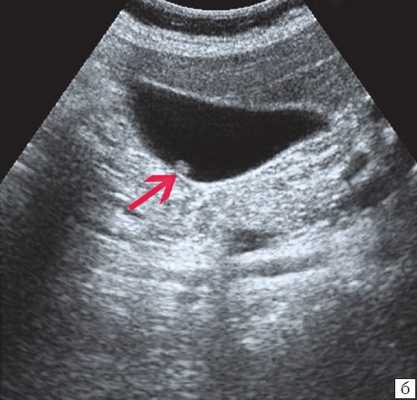

Рис. 4. Гигантская солитарная киста правой почки

Из обследованных детей у 19 обнаружены эхинококковые кисты печени. Для эхиноккокозов печени ультразвуковая картина была достаточно характерной — определялись отдельные кистозные полости размером от 2-3см до 10-12см в диаметре, с четкой капсулой. Стенка кисты состояла из фиброзной и хитиновой оболочек, содержимое — жидкостное. В некоторых случаях определялись дочерние пузыри из зародышевого слоя. Эхинококкоз печени в 3-х случаях сочетался с эхиноккокозом легких; у 1-го — почек. Таким образом, эхиноккокоз внутренних органов достоверно выявлялся при ультразвуковом обследовании.

У 4-х больных отмечался разрыв капсулы эхиноккоковой кисты и излитие содержимого в плевральную полость с развитием плеврита.